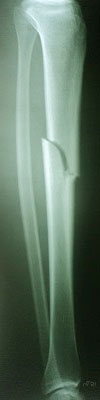

Deteksi tepi adalah langkah kunci dalam identifikasi fraktur. Metode deteksi tepi Canny adalah salah satu teknik yang umum digunakan untuk menemukan tepi dalam citra. Ini bekerja dengan mengidentifikasi perubahan tajam dalam intensitas citra, yang sering terjadi di sekitar tepi objek. Hasil dari langkah ini adalah citra dengan tepi yang lebih tajam dan jelas.

Setelah deteksi tepi selesai, langkah selanjutnya adalah segmentasi citra. Dalam konteks ini, kita ingin mengisolasi area di sekitar fraktur tulang tibia dan fibula. Hal ini dapat dilakukan dengan menggunakan teknik segmentasi berdasarkan intensitas piksel atau dengan teknik lain yang sesuai.